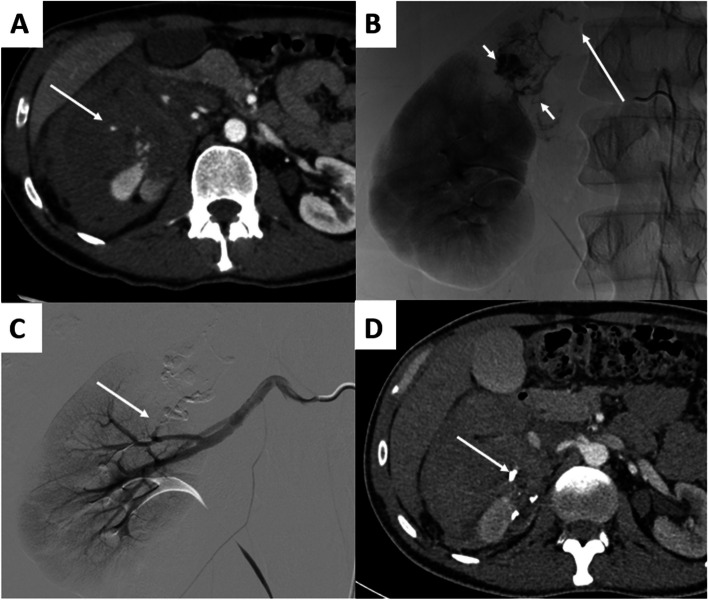

Results: During the inclusion period, 79 procedures were performed. The median age was 60[39-73] years old. On preoperative CT, ≥ 1 pseudoaneurysm was detected in 36(45.6%) patients, and active bleeding in 47(65.8%) patients. The preoperative median haemoglobin rate was 8.9[7.6-11] g/dl, and 37(46.8%) patients required red blood cell transfusions. The main aetiologies of arterial injury were blunt trauma (n = 19) and renal biopsy (n = 17). No severe adverse events were reported. Clinical success was reported in 74(93.7%) of the procedures. Three (3.8%) repeat embolizations were required, and were clinically successful. During the median follow-up of 7[1.5-35.5] months, 9(11.4%) patients died, of which 5(6.3%) occurred within 30 days.

Abstract Image